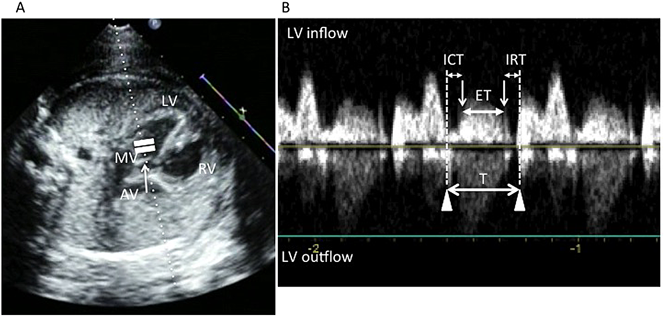

心機能のグローバルな指標である.その簡便性から広く使われている.四腔断面から頭側にプローベを振り上げていくと,左室流出路が描出される(Five Chamber View).Four Chamber ViewからFive Chamber Viewに移行し,かつ僧帽弁構造が描出されるところで僧房弁直下大動脈側にカーソルを設定すると(Fig. 6A),左室流入血流と左室流出血流のドップラーが同時に記録できる(Fig. 6B).左室流入血流の終了時から,次の左室流入血流の開始時までを計測(T),左室流出路血流の駆出時間(ET)を計測し,TとETの差をETで除して求める.TとETの差はドップラー波形から明らかなように,心室に血流の出入りのないいわゆる等容性拡張や等容性収縮時間である.心機能の低下に伴いETが短縮する,または心臓の収縮や拡張が緩慢になり,心室内に血流の出入りのないいわゆる等容性拡張や等容性収縮時間が長くなるため心機能の低下とともに上昇する.弁の動きのドップラーが同時に記録されることが多く,大動脈弁ドップラーからはETが,僧帽弁ドップラーからはTの測定が容易である.右室は解剖学的に同時記録が難しく,心拍数の変わらないところで流入血流と流出血流の別々に記録し,3心拍の平均値から算出する.正常値は左心室0.36±0.06,右心室0.35±0.05で,週数による変化はないとされている11)

Fig. 6 Measurement of the cardiac performance index

A: In the five-chamber view of the fetal heart that is obtained by sweeping the transducer from the level of the four-chamber view towards the fetal head, AV is observed; the cursor is placed just above MV and below AV. B: ET is the interval between the AV opening and closing (white arrows) or the onset and end of the aortic flow. T consists of ICT, ET, and IRT and is measured as the interval between the MV closure and opening, or the end and onset of the MV flow. (AV: aortic valve, ET: ejection time, ICT: isovolumetric contraction time, IRT: isovolumetric relaxation time, LV: left ventricle, MV: mitral valve)